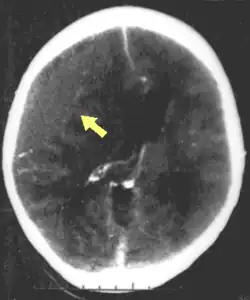

| CT scan showing cerebral contusions, hemorrhage within the hemispheres, and subdural hematoma. There is also displaced skull fracture of left transverse parietal and temporal bones.[2] | |

Hematomas, also focal lesions, are collections of blood in or around the brain that can result from hemorrhage.[11] Intracerebral hemorrhage, with bleeding in the brain tissue itself, is an intra-axial lesion. Extra-axial lesions include epidural hematoma, subdural hematoma, subarachnoid hemorrhage, and intraventricular hemorrhage.[38] Epidural hematoma involves bleeding into the area between the skull and the dura mater, the outermost of the three membranes surrounding the brain.[11] In subdural hematoma, bleeding occurs between the dura and the arachnoid mater.[23] Subarachnoid hemorrhage involves bleeding into the space between the arachnoid membrane and the pia mater.[23] Intraventricular hemorrhage occurs when there is bleeding in the ventricles.[38]

The preferred radiologic test in the emergency setting to determine the severity of a TBI is computed tomography (CT): it is quick, accurate, and widely available.[80] Follow-up CT scans may be performed later to determine whether the injury has progressed.[10]